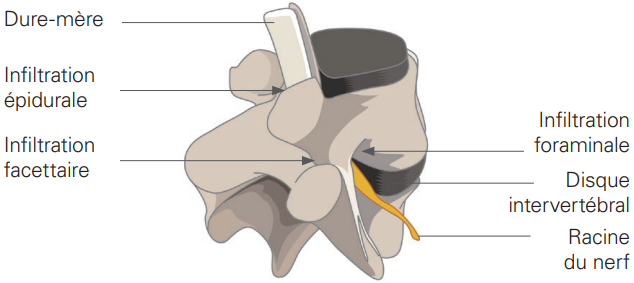

En fonction du site d’injection, on distingue les infiltrations articulaires postérieures (ciblant une ou plusieurs articulations unissant 2 vertèbres) par abord direct ou via leur innervation (bloc de branche médiale), épidurales (ciblant un espace interne de la colonne vertébrale), ou péri-radiculaires (ciblant le nerf sortant de la colonne vertébrale) pour les plus communes.

Pour ce qui est du rachis/colonne vertébrale, il existe deux types d’infiltration :

- Infiltration épidurale ou foraminale : injection en regard de la zone de conflit entre les nerfs (nerf crural ou sciatique) et les disques et/ou les structures osseuses. Pour l’infiltration épidurale l’injection est faite dans l’espace graisseux entre la dure-mère contenant la vertèbre osseuse et les nerfs. Dans de rares situations, l’infiltration est réalisée dans le foramen vertébral (région par laquelle les nerfs « sortent » du canal lombaire).

- Infiltration facettaire ou articulaire postérieure : articulation vertébrale souvent associée à des poussées inflammatoires d’arthrose vertébrale